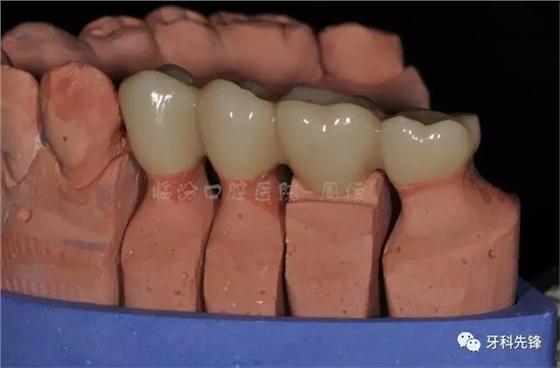

圖13牙體預(yù)備模型照

圖14臨時(shí)牙